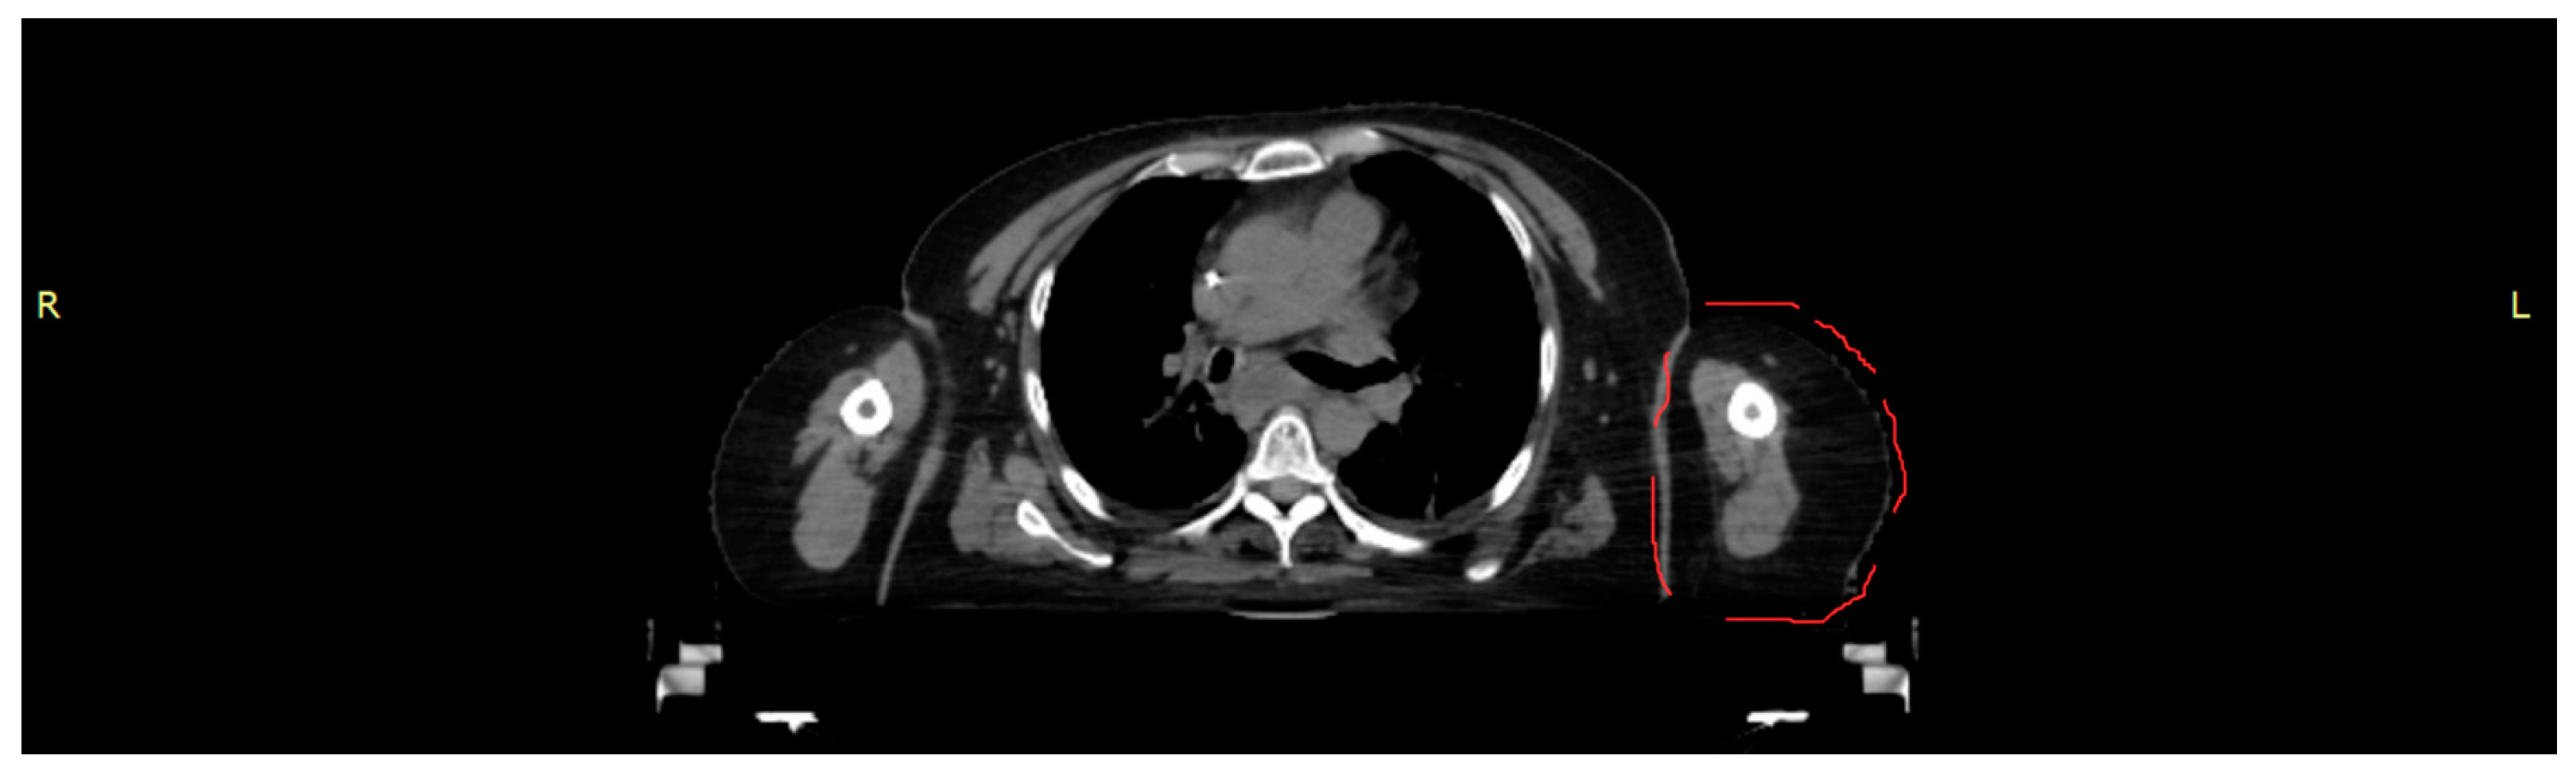

A CT scan of a female torso, acquired on a Brilliance CT Big Bore Oncology scanner (Philips, Hamburg, Germany) operating at 290 mA and 120 kV, was used to obtain the data for both morphology and density values as the basis for an anthropomorphic phantom representing part of the left upper arm (

Figure 1). Based on density (CT numbers), the images were segmented in 3D Slicer (Alliance for Medical Image Computing (NA-MIC), Boston, MA, USA) into tissue classes corresponding to skin, cortical bone, bone marrow and soft tissue. The segmented tissues were exported as Standard Transformation Language (STL) files.